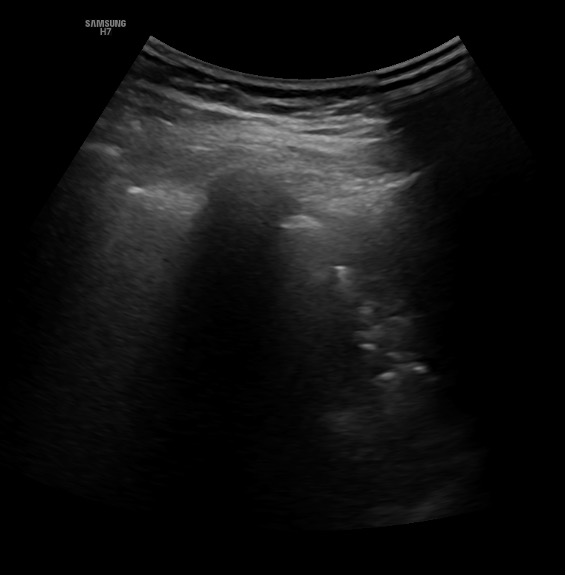

Ecografía clínica pulmonar: infiltrado en base izquierda con mínimo derrame y características de broncograma dinámico. Derrame pleural derecho de escasa cuantía con signo de la medusa.

La paciente ingresa en planta por insuficiencia respiratoria. Gracias a la ecografía clínica se objetivó en base izquierda una imagen compatible con neumonía basal izquierda. Al alta la paciente presenta mejoría clínica, ventilatoria, oximétrica y analítica con buen estado general. Eupneica en reposo y afebril.